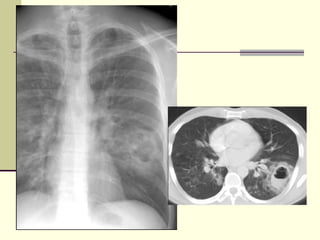

Dissecting aortic aneurysm

Left-sided Pleural Effusion 1. Dissecting aortic aneurysm 2. Pancreatitis 3. Distal thoracic duct rupture 4. Esophageal pathology